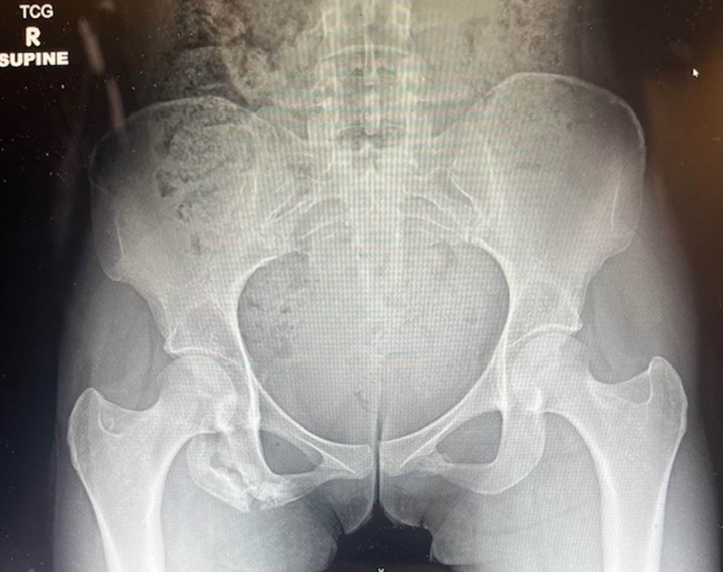

Not So Typical Hip Dislocation

A 20-year-old female presents to the ED after MVC with left hip pain. Notably her leg was up on the dash of the car when the accident occurred. Unable to ambulate since the accident and her pain is constant and worse with attempted movement. She notes muscle spasms around her left hip region. She was lying on the stretcher with the affected lower extremity abducted, slightly flexed and externally rotated without obvious shortening. On log roll testing she reported significant pain especially in the anterior groin region.

Snap and Shift: The Hip Avulsion Saga

A 15-year-old male presented to the emergency department with acute left hip pain after playing basketball. The patient experienced a sharp pain in the left anterior hip after making an abrupt twisting movement while trying to take the ball from his opponent and is now unable to bear weight. He denies numbness, tingling, or other traumas, but reports left leg weakness and pain.